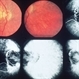

- Fundus photograph and autofluorescence of a 49 year old male with mucopolysaccharidosis type III (Sanfilippo syndrome)